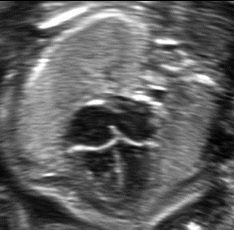

What is the feral lie based on the anatomy showed?

Vertex spine down